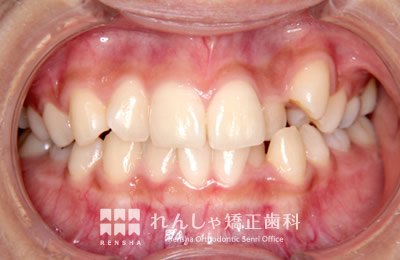

大きながたつきを歯列の拡大で改善しようとすると歯周組織へのダメージや後戻りが問題になります。この様な場合はスペースを確保するために永久歯を抜歯する方法を選択します。歯を抜いてしまうことに不安もあるかと思いますが、抜歯矯正が長い目で見たときにいい結果になることも多いと思います。

治療前

→

治療後

| 主訴 | 叢生 |

|---|---|

| 診断名 | Angle Class I 叢生 |

| 初診時年齢 | 27歳0か月 |

| 装置名 | マルチブラケット装置 |

| 抜歯非抜歯 | 上下顎左右第一小臼歯の抜歯(合計4本) |

| 治療期間 | 2年5か月 |

| 費用の目安 | 約93万円+消費税(検査料金、都度の処置費用等も合わせた総額) |

| リスク副作用 | 歯の移動に伴う軽微な歯根吸収、歯槽骨吸収、歯肉退縮(本症例では軽度の歯肉退縮を認めた)、矯正器具装着中のカリエスリスク増大(本症例ではカリエス発生無し) |